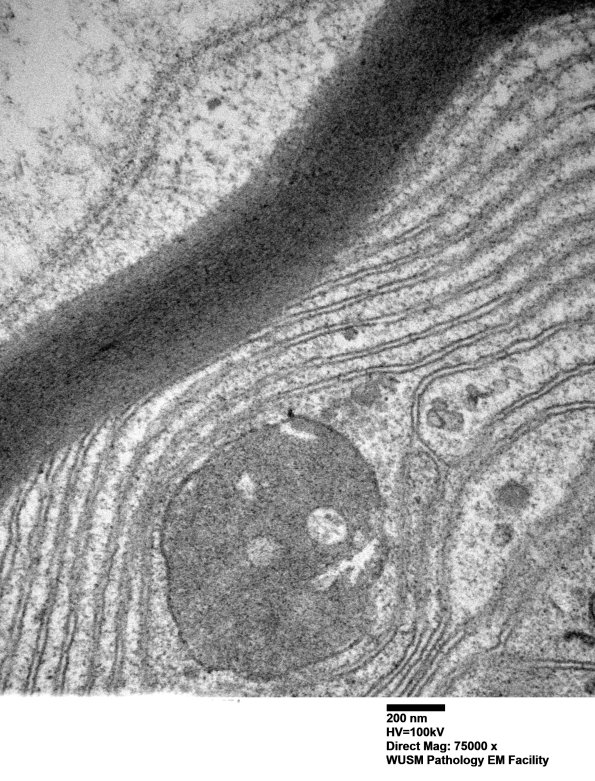

1B1D,E High magnification images of the origin of separation of myelin lamellae. (electron micrographs)